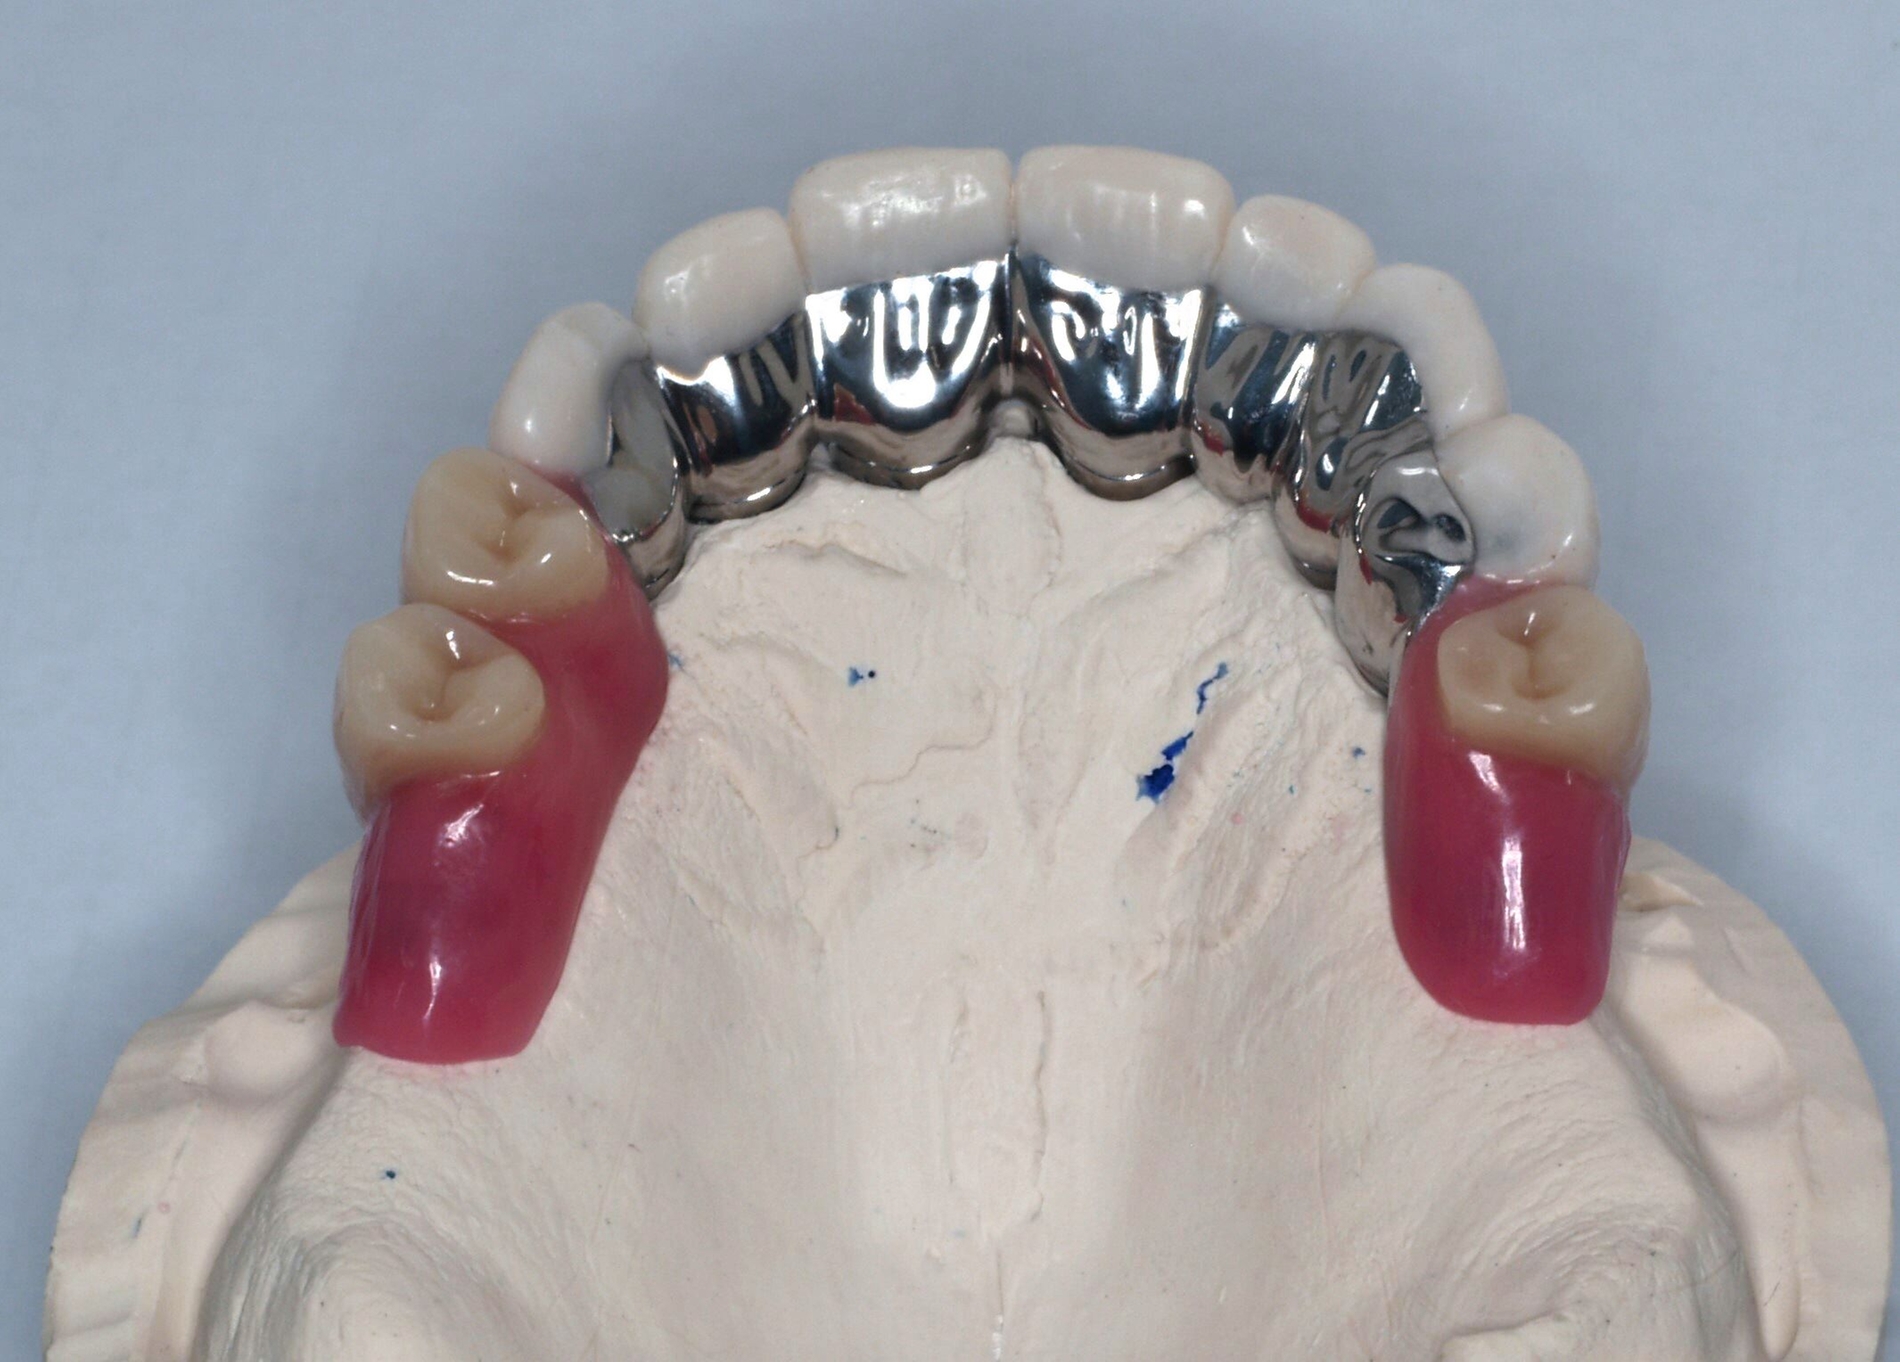

Die Stümpfe wurden folglich zur Aufnahme von Teleskopkronen präpariert und mittels Doppel-Fadentechnik für die konventionelle Abformung mit dem Polyether vorbereitet. Nachdem das zahntechnische Labor die NEM-Primärteleskope hergestellt hatte, wurden sie am Patienten anprobiert und mit einem Tropfen provisorischen Zements auf den Stümpfen fixiert (Abbildung 5a), um sie anschließend in der Fixationsabformung mit abzuformen (Abbildung 5b).

Auf dem Meistermodell wurde vom Labor nun der Wachswall zwecks Kieferrelationsbestimmung hergestellt. Nach Überprüfung der Ruheschwebelage von 2 mm wurde der Wachswall verschlüsselt. Bei der Gesamtanprobe konnte neben der Kontrolle der statischen/dynamischen Okklusion und der Ästhetik das spannungsfreie Gleiten des Prothesengerüsts in die Primärteleskope überprüft werden.

Schließlich erfolgte die Eingliederung der fertigen Teleskopprothese (Abbildung 6). Die Primärteile wurden mit Glasionomerzement auf den Stümpfen zementiert. Nach Entfernung der Zementreste und der erneuten Überprüfung der statischen und der dynamischen Okklusion, ist das gemeinsame Üben des Ein- und Ausgliederns der Prothese gerade bei dieser Art der Arbeit unabdingbar. Eine ausführliche Aufklärung über die Reinigung, Handhabung und das Recall folgte.